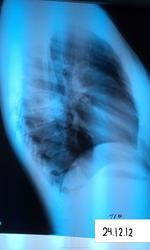

Пациентка, 19 лет, поднялась температура 15, 16 декабря, возможно раньше, до 39 градусов. Сделали рентген, выставили пневмонию S6 справа. Лечили от пневмонии, состояние улучшилось. Сегодня мой коллега выставляет туберкулез, т.к. распад. Ваше мнение, уважаемые коллеги? Благодарю

Это не туберкулез, туберкулез так быстро на терапию не откликается. S6 лучше томографировать в боковой проекции.

Тоже за пневмонию

пациентку в противотуберкулёзный диспансер. Особенно на новогодние праздники. Данные  рентгенологического исследования, высокая температура тела, быстрая положительная динамика изменений в легких указывает на пневмонию. Пневмония может быть деструктивной. Дело сейчас за терапевтами. Они должны оценить весь комплекс первичного обследования  и  решить для себя, это пневмония или нет. Тезис "пневмония-диагноз не рентгенологический, а клинический"  не потерял своего значения сегодня. Т.К. процесс находится в 6 сегменте, то надо быть начеку, но весь минимум исследования на туберкулез необходимо выполнить в общей лечебной сети. Пересмотреть терапию, если это необходимо. Известно, что воспалительные процессы в 6 сегменте любой этиологии рассасываются медленнее. Таково мое мнение. После 9.1.13 г. покажите нам контроль.

Это пневмония.Туберкулез не даст такой быстрой положительной динамики при любом лечении , в том числе фторхинолонами.А вот историю болезни не позволяйте скрывать от Вас.

Спасибо, уважаемые коллеги! Очень ценно ваше мнение. А распад ведь есть? Мой опытный коллега считает что так быстро может только туберкулез распадаться

Так быстро-пневмония,вероятно-гнойная.Туберкулез-процесс медленный.Исключение-сочетание с ВИЧ. Но это не здесь.

+1. ИМХО: собственно говоря, не вижу убедительных признаков распада. R-ски: больше данных за пневмонию. Дифференцировать с туберкулёзом.

Я тоже за пневмонию, на tbc не похоже. Распад сомнителен. Нужен клинич. и R-лог. контроль 9-10 янв.

сначала было уплотнение по типу консолидации ,ко-ое после лечения трансформировалось в синдром круглой тени,на ее фоне сохраняются интерстициальные изменения  -туберкулема  таких размеров редкость ,контуры нечеткие(интерстициальные изменения ),распад эксцентричный,стенки неравномерные по толщине .в д.д. добавлю периферическое новообразование